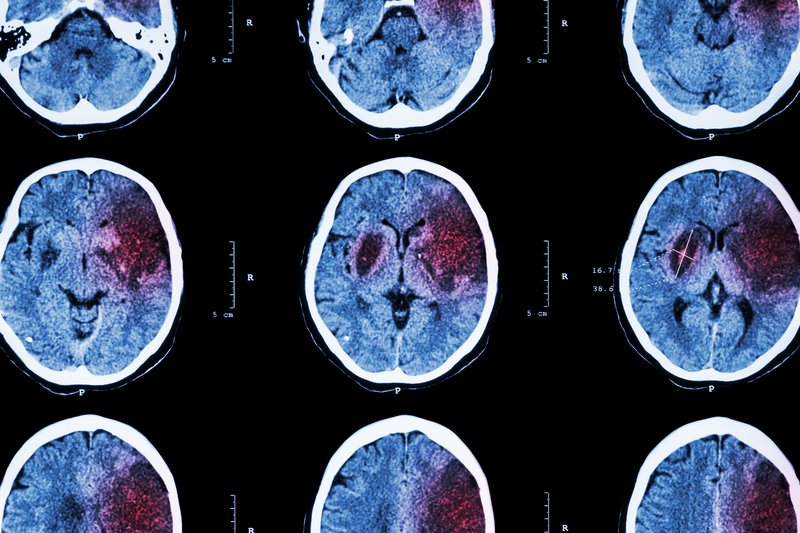

Najczęstszą postacią udaru jest udar niedokrwienny. Powstaje on w wyniku zaburzenia dopływu krwi do mózgu, gdy duża lub mała tętnica wewnątrz narządu ulegnie zamknięciu albo zostanie zwężona. W następstwie do części mózgu nie dopływa krew z tlenem. Udar ten nazywa się poniekąd zawałem mózgu, ponieważ jego przebieg przypomina zawał serca.

Drugim z typów udaru jest udar krwotoczny, zwany popularnie wylewem. W tym przypadku dochodzi do wylewu krwi do mózgu na skutek pęknięcia naczynia. Udar ten jest zdecydowanie groźniejszy od tego niedokrwiennego – częściej kończy się on śmiercią lub kalectwem.

Postać krwotoczna udaru może być skutkiem m.in. nadciśnienia tętniczego, pęknięcia tętniaka lub doznanego urazu głowy.